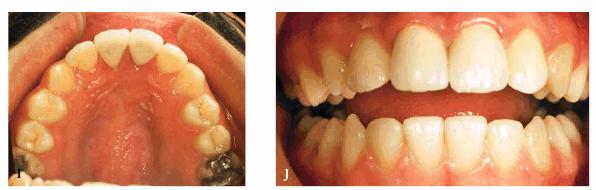

preparations were made, and impressions for aluminous porcelain crowns were

made. The two crowns were seated (Figur 323s1823d es 18-7I

and J Figur 323s1823d e 18-7K is a radiograph of the teeth at the

end of treatment.

Figur 323s1823d e 18-7I and J: Two aluminous porcelain crowns were constructed and inserted on the central incisors.

Figur 323s1823d e 18-7K: Post-treatment radiograph of the two fractured and restored central incisors.